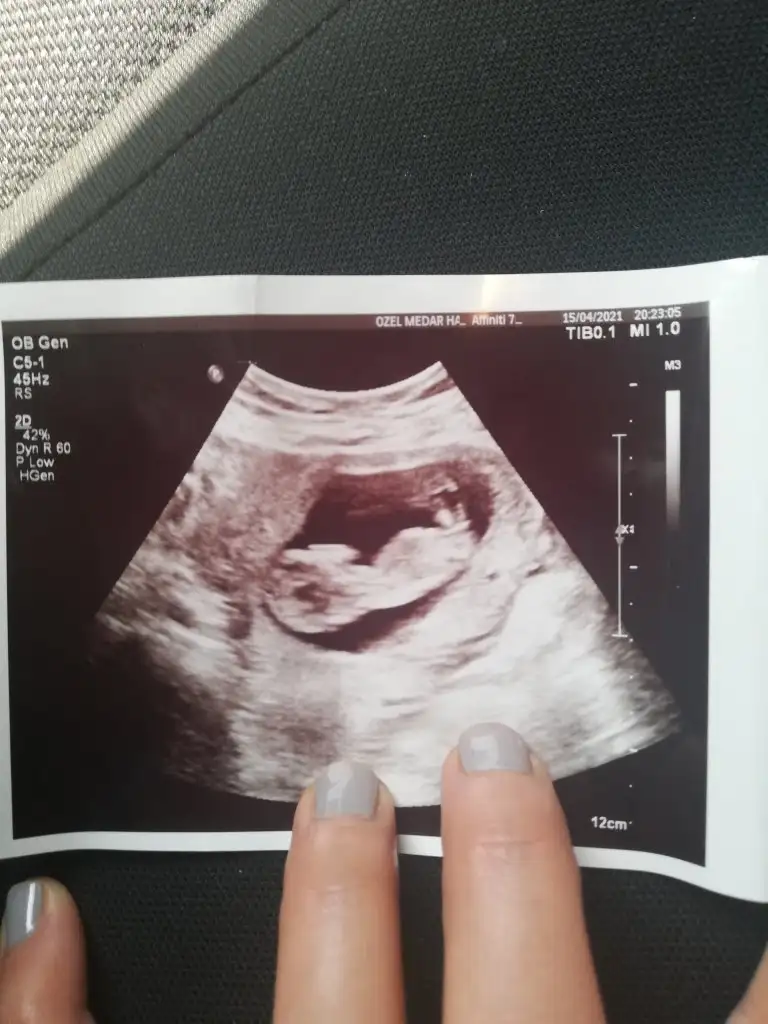

Merhaba benim ultrasonuma da bakar mısınız 12+2 😌

Kafasının hemen altındaki kordonu canim 😊 bana da erkek gibi geldi sanki ultrasonda seyredince pipisi dik gibi geldi ama bakalım yazicam sana tekrardan .çok sağol canım .2hafta sonra Dr tahmin etmezse yyeni foto atarım .

Olabilir cnm emin olamadım 🙈 Baska USG yokmu 10-11-12